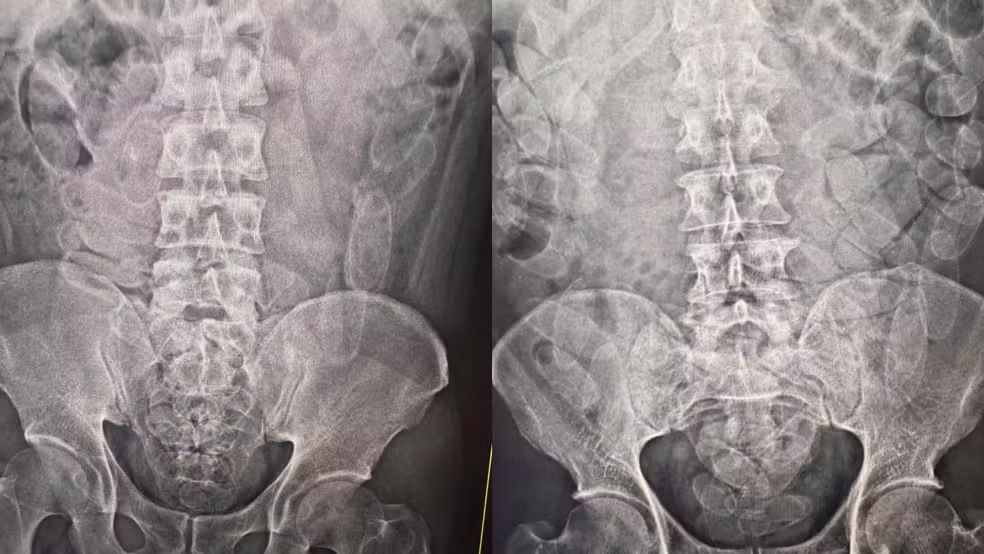

O trio foi encaminhado para a Santa Casa de Corumbá, onde foram realizados exames que confirmaram a suspeita. Os três engoliram cerca de 100 cápsulas da droga, aproximadamente 3,5 kg. A cocaína foi expelida e os presos encaminhados para a Polícia Federal.